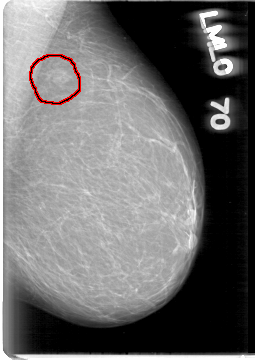

D_4003_1.LEFT_CC

LEFT_CC LINES 5191 PIXELS_PER_LINE 3346 BITS_PER_PIXEL 12 RESOLUTION 43.5 OVERLAY

FILE: D_4003_1.LEFT_CC.OVERLAY

TOTAL_ABNORMALITIES 1

ABNORMALITY 1

LESION_TYPE MASS SHAPE IRREGULAR MARGINS OBSCURED

ASSESSMENT 0

SUBTLETY 4

PATHOLOGY BENIGN

TOTAL_OUTLINES 1

BOUNDARY